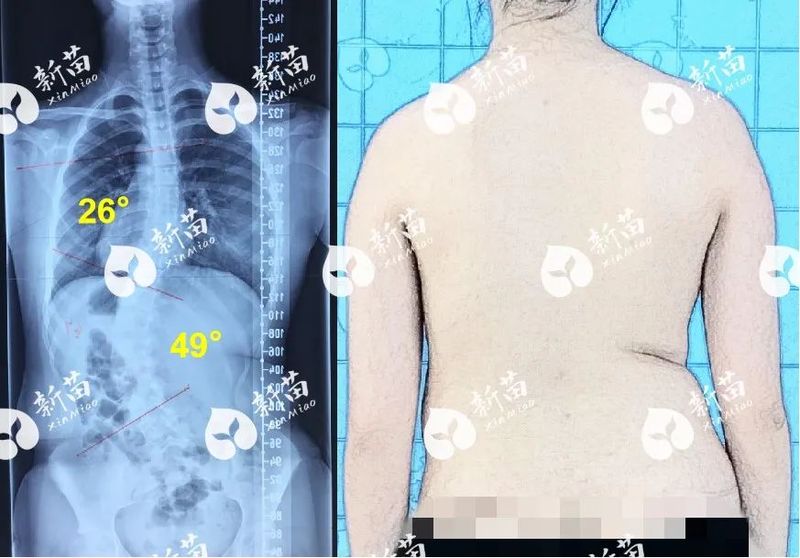

初二女生每天堅持訓(xùn)練,成功“掰直”49°側(cè)彎!

13歲的小沐(化名)自小就很乖巧,學(xué)習(xí)成績優(yōu)異,一直是父母心中的驕傲。然而,一次偶然的發(fā)現(xiàn)讓這個幸福的家庭如遭雷擊——小沐被診斷出患有脊柱側(cè)彎,而且主彎角度高達(dá)49°!當(dāng)時很多醫(yī)生都建議手術(shù)治療,但小沐父母不想孩子年紀(jì)輕輕就“挨一刀”。通過網(wǎng)上查詢,他們找到了脊柱側(cè)彎領(lǐng)域的權(quán)威專家楊軍林教授。經(jīng)過全面檢查和評估,楊教授建議“先嘗試佩戴支具配合形體訓(xùn)練3個月”,這句話成了全家最后的希望。治療故事分享每天擠出時間鍛煉,從不叫苦叫累醫(yī)學(xué)形體訓(xùn)練是側(cè)彎矯正過程中至關(guān)重要的一環(huán)。當(dāng)時正讀初二的小沐在繁重的學(xué)業(yè)之余,每天都要擠出2個小時進(jìn)行訓(xùn)練,有時候晚上10點半才做完作業(yè),但還是要堅持鍛煉一個小時。母親心疼地說:“孩子真的特別能吃苦,從來沒有叫苦叫累過,她知道只有堅持訓(xùn)練,才能讓身體恢復(fù)健康?!痹谥委熯^程中,父母的陪伴與支持也很關(guān)鍵。每晚訓(xùn)練時,母親都會陪在小沐身邊,為她掐秒表計時,確保每一個動作既達(dá)到標(biāo)準(zhǔn)又完成規(guī)定的量。她不僅時刻關(guān)注著女兒的身體和心理狀況,還經(jīng)常鼓勵女兒說:“只要我們堅持下去,一定會看到希望的?!闭怯辛四赣H的愛和鼓勵,小沐在矯正之路上才能越走越堅定。從49°到21°,所有付出都是值得的堅持治療4個月后,小沐前來復(fù)診拍片,結(jié)果顯示主彎從49°減到29°,這讓小沐一家非常驚喜!因為足足恢復(fù)了20°,小沐原本緊繃的神經(jīng)一下子放松下來,后面佩戴支具就有點松懈,結(jié)果在第二次復(fù)診時,度數(shù)又反彈至37°。這次教訓(xùn)讓全家意識到支具規(guī)范佩戴的重要性。此后,小沐每天佩戴支具時都嚴(yán)格按要求拉緊,同時堅持不懈地進(jìn)行形體訓(xùn)練。到了第三次復(fù)診拍片時,主彎已經(jīng)成功降至21°,外觀也有了顯著的改善。母親激動地說:“看到她現(xiàn)在的樣子,我真心覺得所有的付出都是值得的。真的非常感謝楊教授和他的團(tuán)隊,如果不是他們開創(chuàng)了大角度側(cè)彎的保守治療體系,我女兒可能就要做手術(shù)了,他們真的拯救了很多孩子!”醫(yī)生點評患者治療前13歲,Risser征1級,主彎腰左彎Cobb角49°,軀干向左偏移,高低肩明顯,右側(cè)腰線往內(nèi)凹陷,已具手術(shù)指征。結(jié)合影像、查體及柔韌性等評估,建議支具結(jié)合醫(yī)學(xué)形體、強(qiáng)化康復(fù)的綜合保守治療。患者年齡小,主彎在腰部,彎曲節(jié)段長,柔韌性較好,支具下主彎矯形率高,并且其治療依從性高,積極配合新苗XTS體系全過程治療監(jiān)控和中長期動態(tài)調(diào)整治療。整體治療在控制側(cè)彎進(jìn)展和體態(tài)方面效果顯著:主彎從49°矯正至21°,好轉(zhuǎn)57%,外觀基本恢復(fù)對稱。通過保守治療,完整地保留患者的脊柱活動功能,避免了手術(shù)對腰椎活動功能的影響。目前患者的Risser征4級,已度過快速生長期,骨骼發(fā)育基本穩(wěn)定,快速進(jìn)展的風(fēng)險降低。后續(xù)需遵醫(yī)囑堅持治療,并定期復(fù)診,在鞏固目前治療效果的基礎(chǔ)上,進(jìn)一步矯正側(cè)彎,恢復(fù)健康體態(tài)。